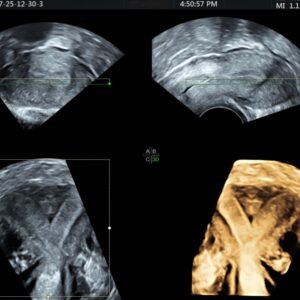

Omogućava detaljan trodimenzionalni prikaz anatomije i morfologije maternice i jajnika. Vrlo  je koristan u dijagnostici anomalija maternice (jednoroga maternica, septum itd).

3D ULTRAZVUK